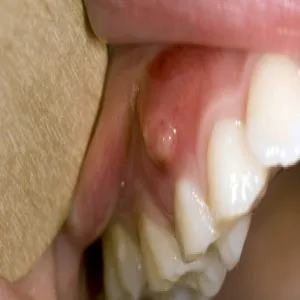

Nadziąślak

Nadziąślak, epulis